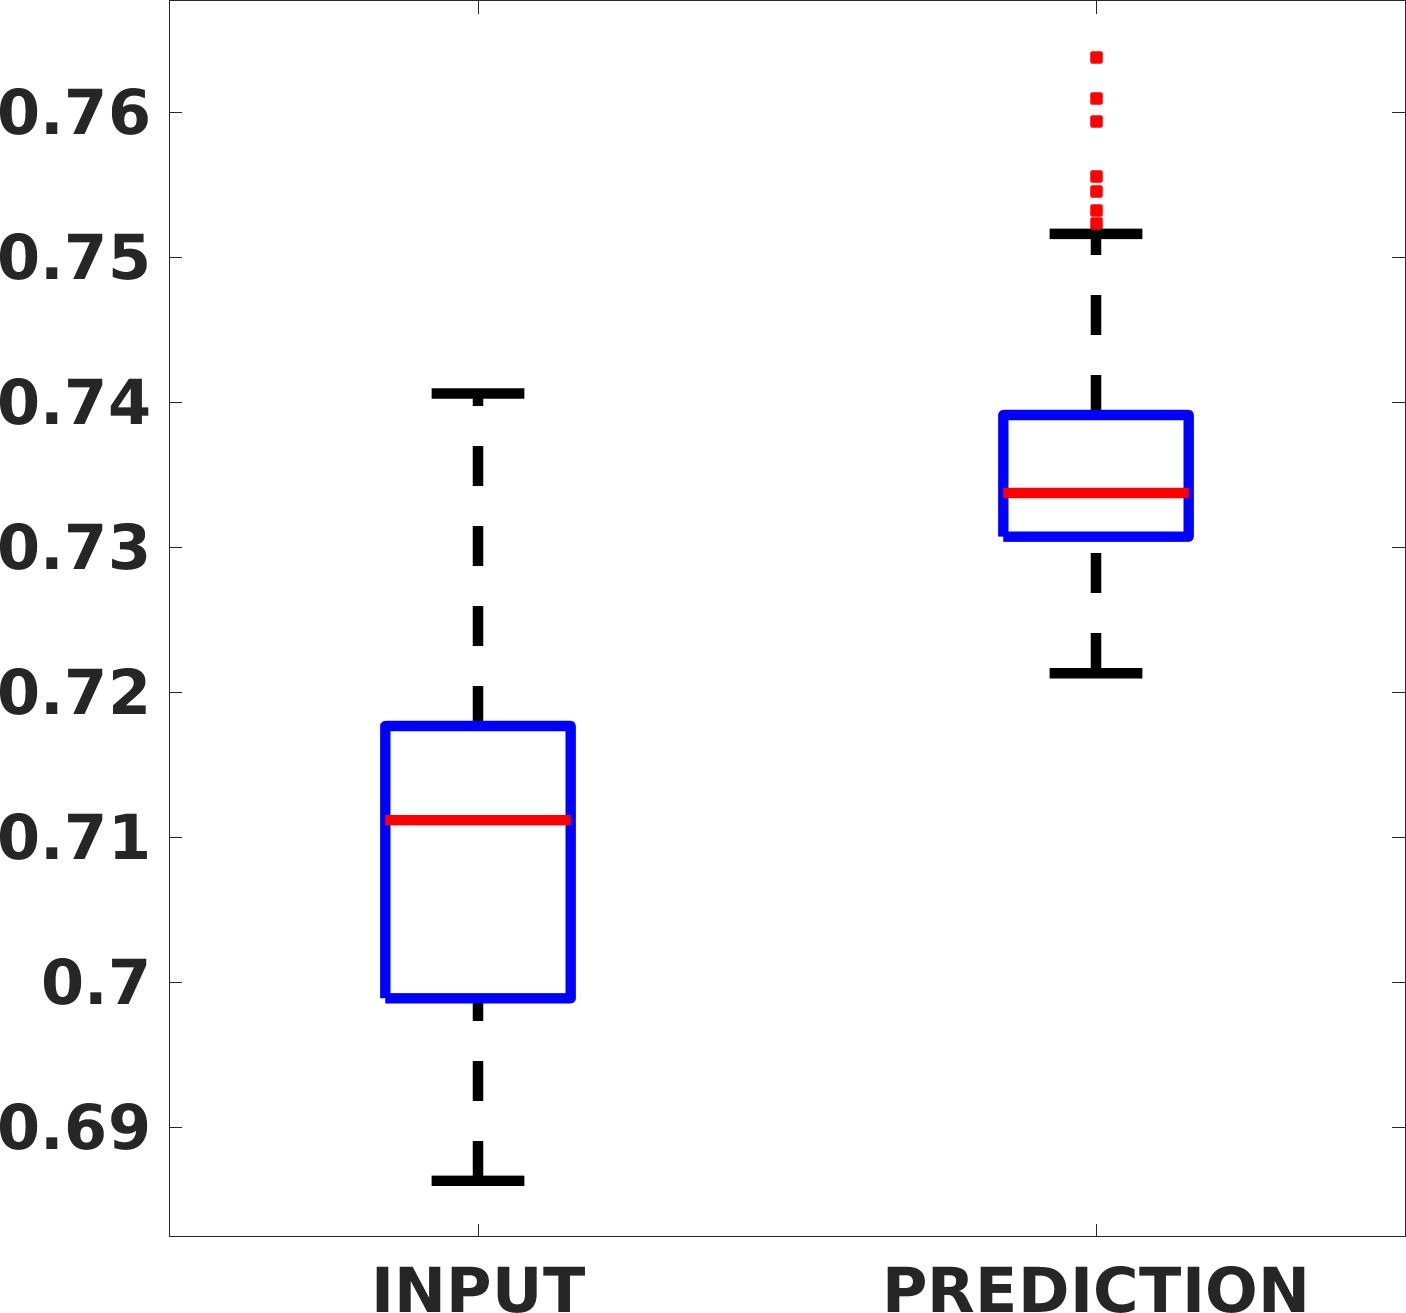

Fig. 7(a-b-c, left) shows the box plot of the statistics of the PSNR on three different anatomical districts, comparing the target images with the prediction and the cubic convolution, respectively. The metrics are computed on a data set of 200 images of the same district and with the same up-sampling factor. We report that the PSNR median value improves of on obstetric 2X raw images, on cardiac 2X raw images, and on abdominal raw 4X images.

Fig. 7(a-b-c, right) shows the histogram of the absolute value of the error with respect to the target image, of the prediction and Cubic convolution results, respectively. The histograms show the number of pixels where the prediction error is lower than 5 (i.e., the first bin of the histogram), which means very similar to the target when visually analysing the images. From the Cubic convolution to the predicted images, this value increases of on obstetric 4X raw images, on cardiac 4X raw images, and on abdominal 4X raw images.

Fig. 8 shows the box plot of the SSIM (a-b-c, left) and MAE (a-b-c, right) quantitative metrics, as performed for PSNR metric. Also, these metrics show that our method improves the results of Cubic convolution both in terms of average value and variability. For example, the SSIM median value improves of on obstetric 4X images and the MAE median value improves of on cardiac 2X images.